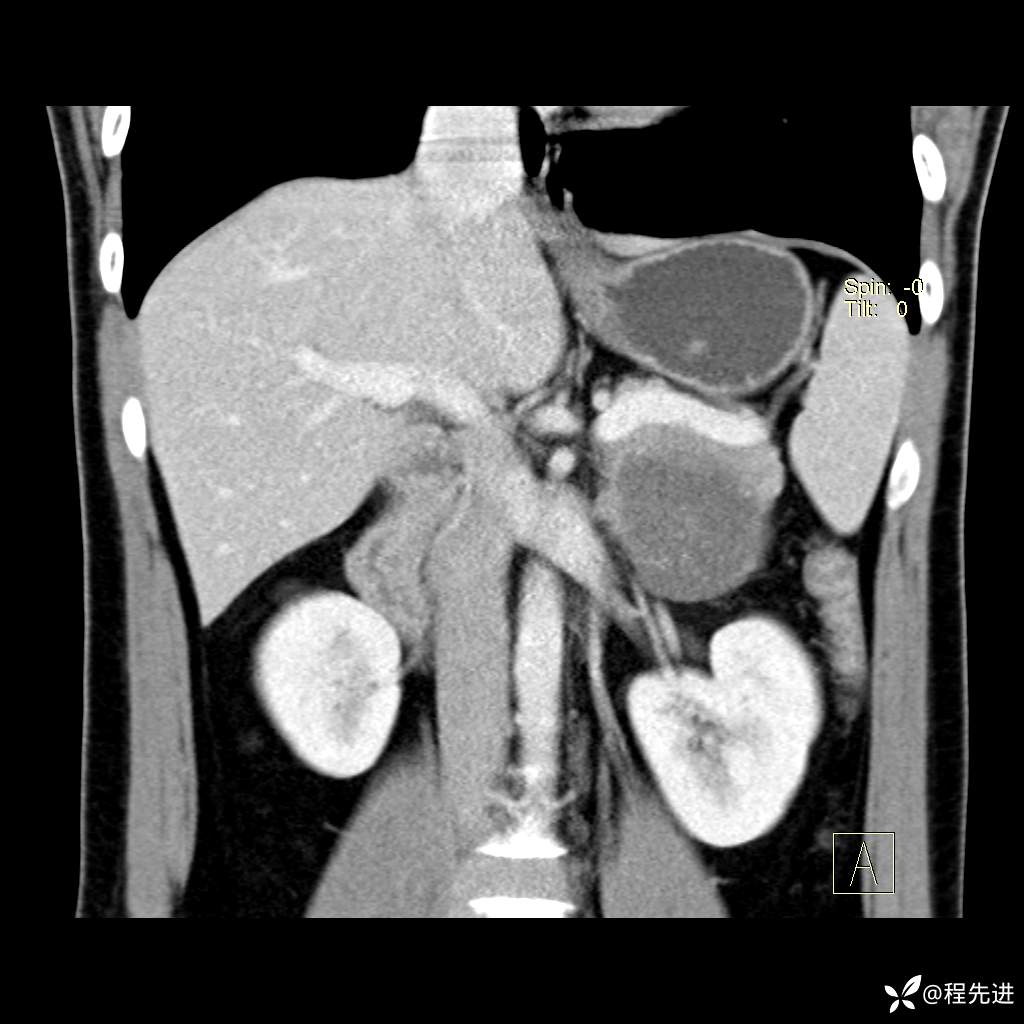

CT平扫:(CT值:平扫,27HU,动脉期,27HU,门静脉期,31HU,平衡期,32HU)

冠状位重建: